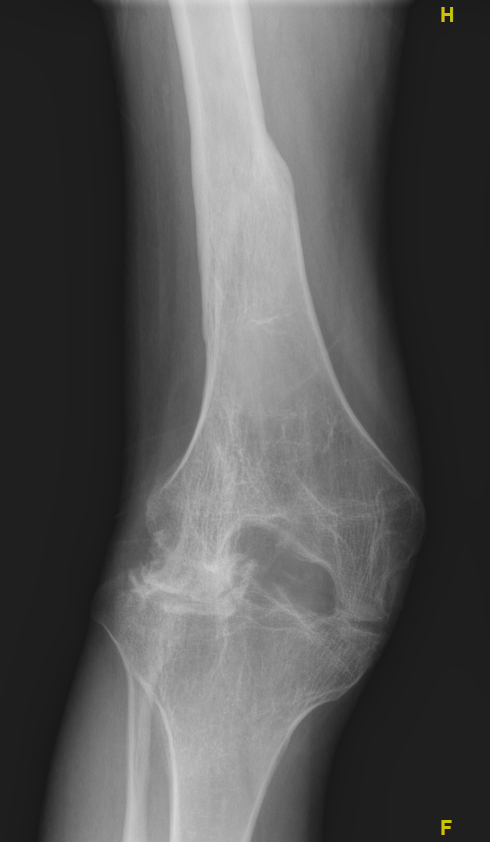

3、影像学检查

检查结果显示右下肢外翻畸形15度,股骨远端关节外畸形5度,髌股关节骨性融合,膝关节畸形发育。